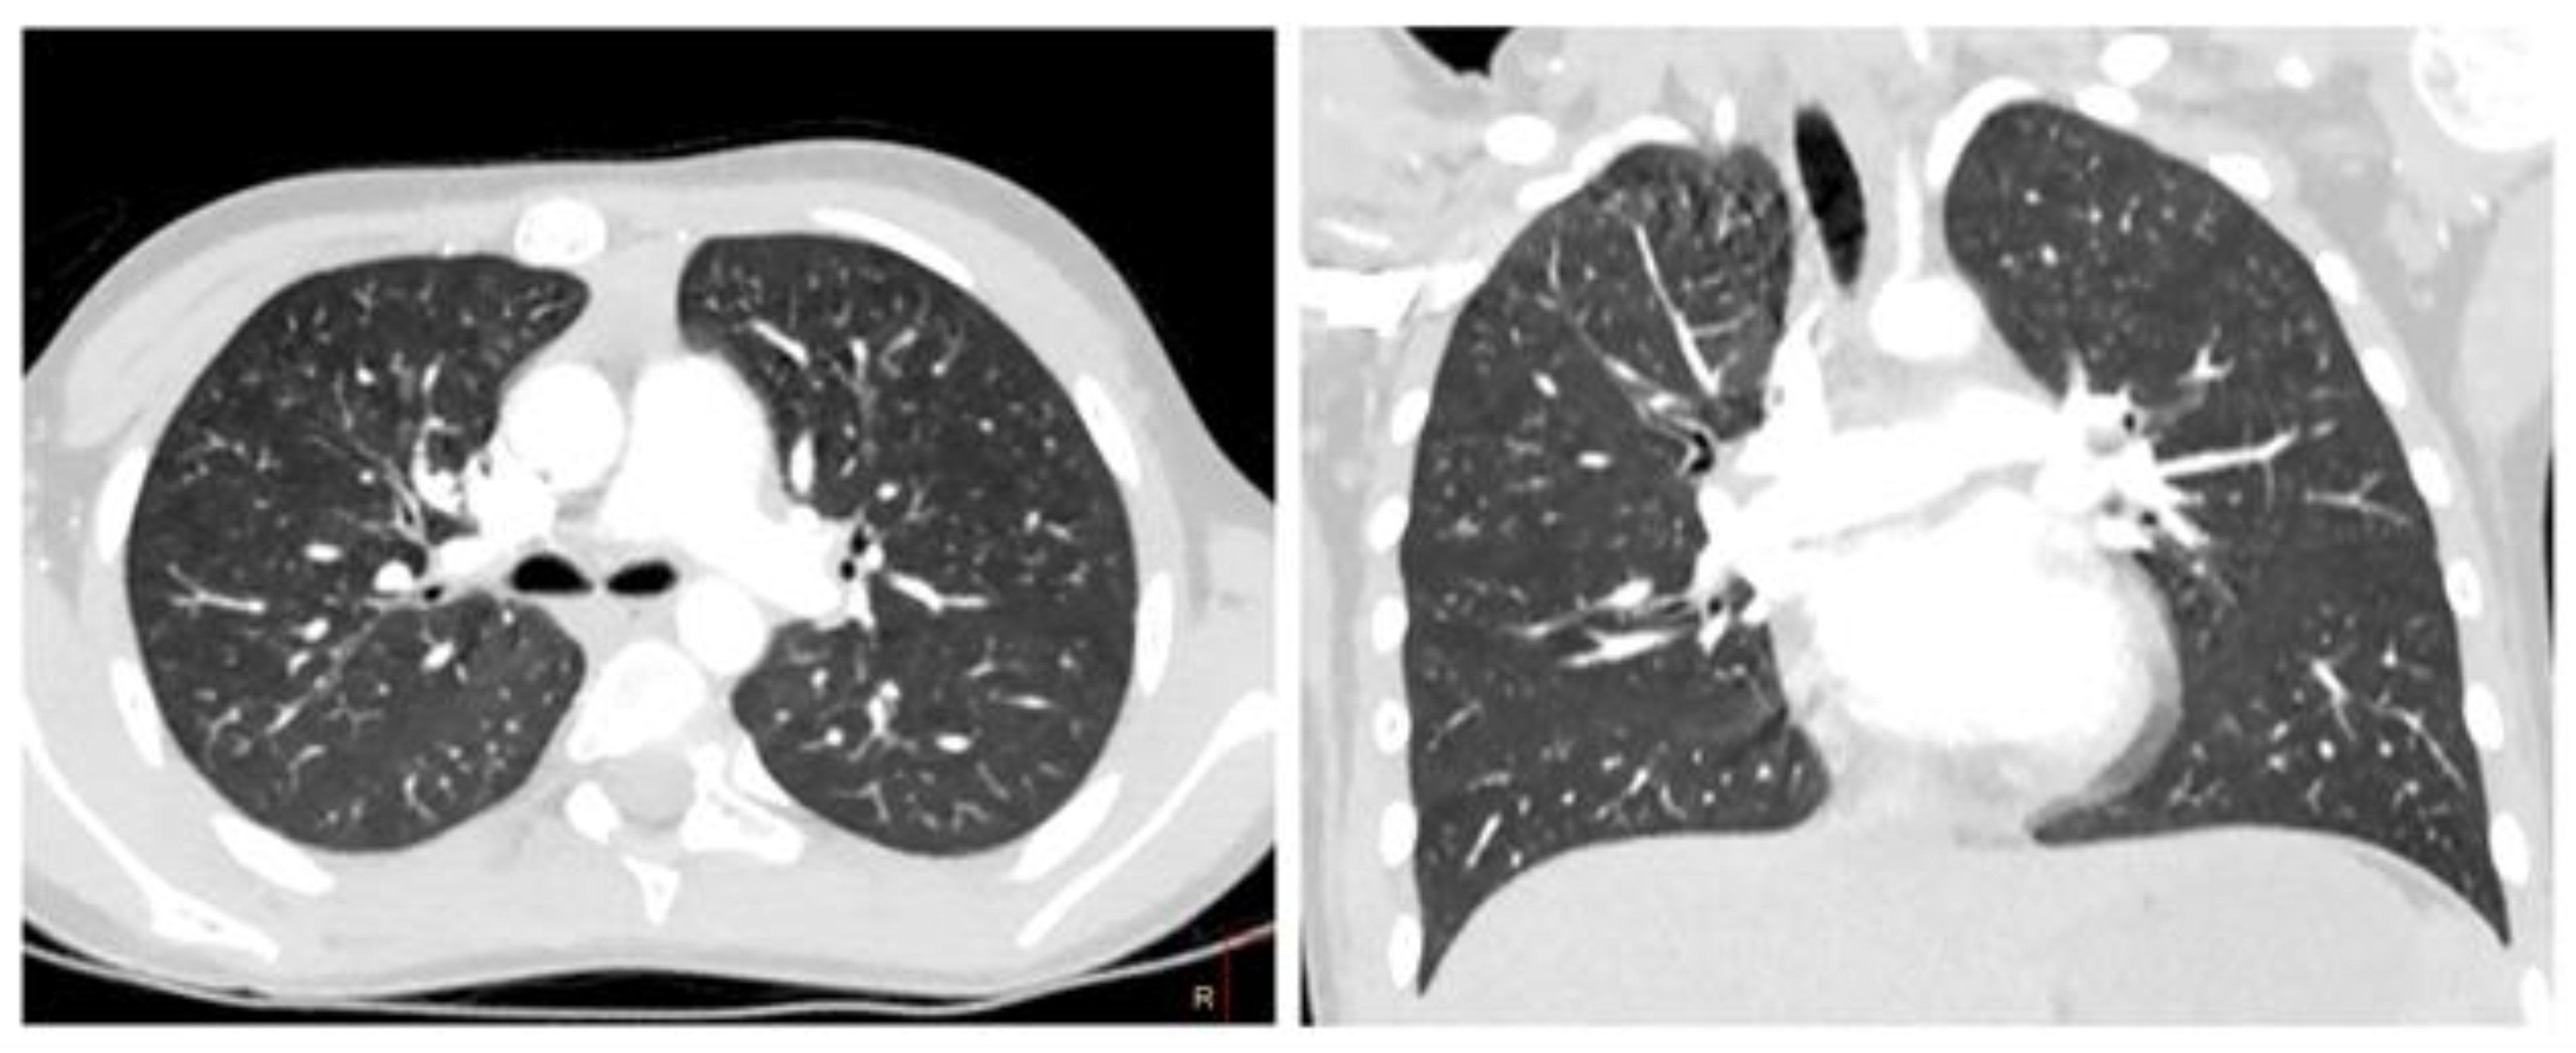

2. Case 1

2.1. Examination Data

2.2. Substantiation of Diagnosis

3. Case 2